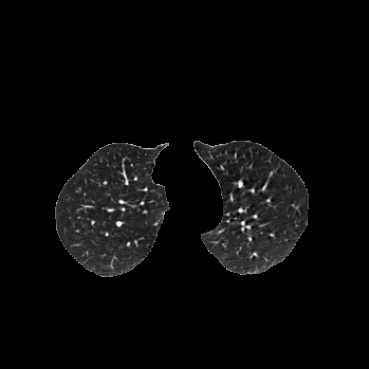

COPDGene / Dirlab lung CT. We follow the data selection and preprocessing of [23]. We train on 999 inhale/exhale pairs from COPDGene [18], masked with lung segmentations, clipped to [-1000, 0] Hounsfield units, and scaled to (0, 1). We evaluate landmark error (MTRE) on the ten inhale/exhale pairs of the Dirlab challenge dataset [4]333https://tinyurl.com/msk56ss5.

| Moving Image | Warped Image | Fixed Image | Moving Image | Warped Image | Fixed Image |